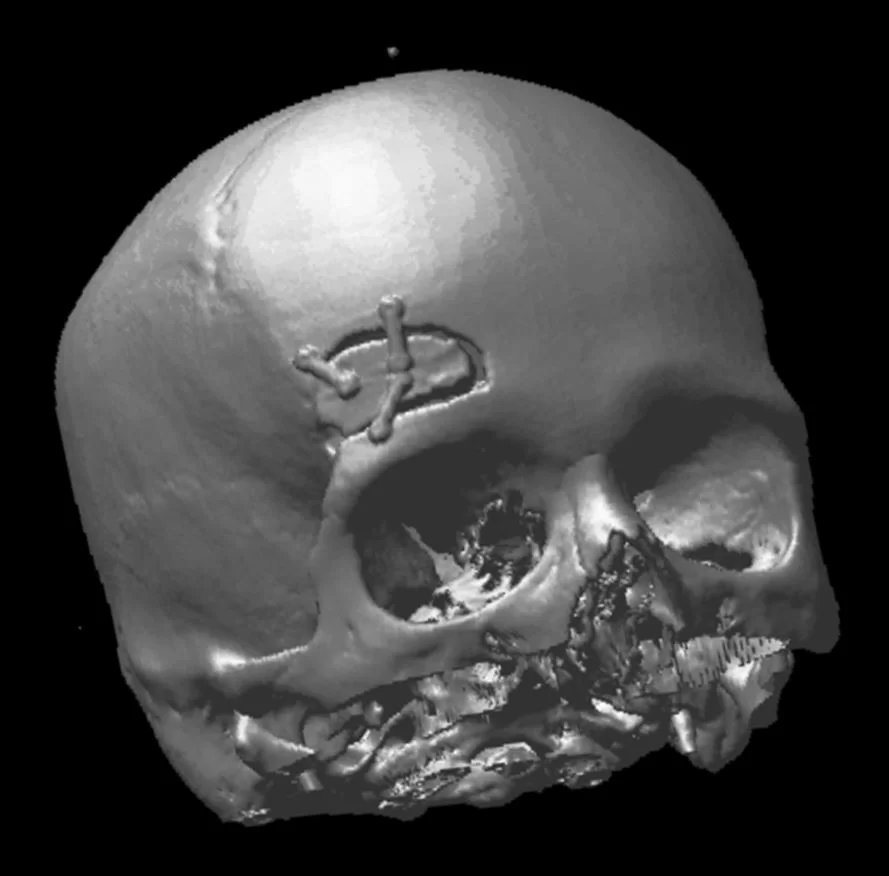

Δερμοειδής όγκος κροταφικά αριστερά

Ασθενής άνδρας, 66 ετών με ιστορικό χειρουργηθείσας εξεργασίας (δερμοειδές) το 1991. Στους μετεγχειρητικούς ελέγχους αναδείχθηκε υποτροπή και προοδευτική άυξηση της χωροκατακτητικής εξεργασίας αριστερά κροταφικά. Η